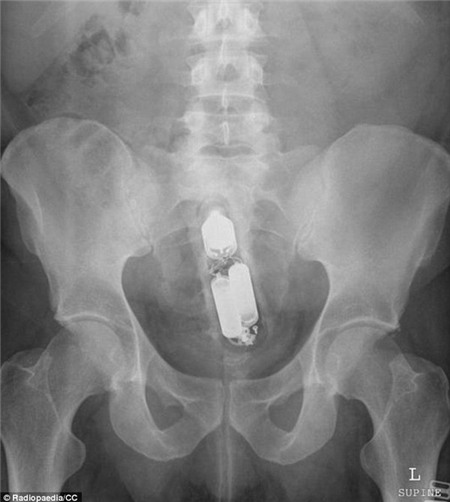

Trong khi đó, một bệnh nhân khác lại có một chiếc máy rung ở hậu môn.